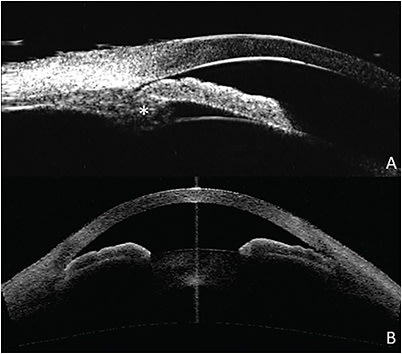

Many of the angle parameters that can be measured on OCT can also be assessed with UBM, with some additional ones such as iris-lens contact distance (ILCD) and trabecular-ciliary process distance (TCPD) made possible by the increased depth of imaging.28 UBM has demonstrated a similar sensitivity, specificity, and AUC as OCT for distinguishing narrow from open angles, but values between the 2 modalities show poor agreement for individual measurements.29,30 Because of the ability to image the ciliary body, UBM serves an important role in diagnosing plateau iris (Figure 3). Ultrasound biomicroscopy studies have shown that plateau iris is present in 32% to 37% of PACD eyes that have undergone LPI, with the condition being more common in younger patients and females. Parameters including AOD500, AOD750, ACD, ACA, TCPD, and ILCD are significantly smaller in plateau iris eyes compared to PACD eyes. Plateau iris is also more likely to be found among eyes with severe PACG and to have a greater extent of peripheral anterior synechiae.31,32 Given the poor diagnostic performance of OCT for detecting plateau iris,33 UBM remains necessary to detect this significant risk factor for more advanced glaucoma.